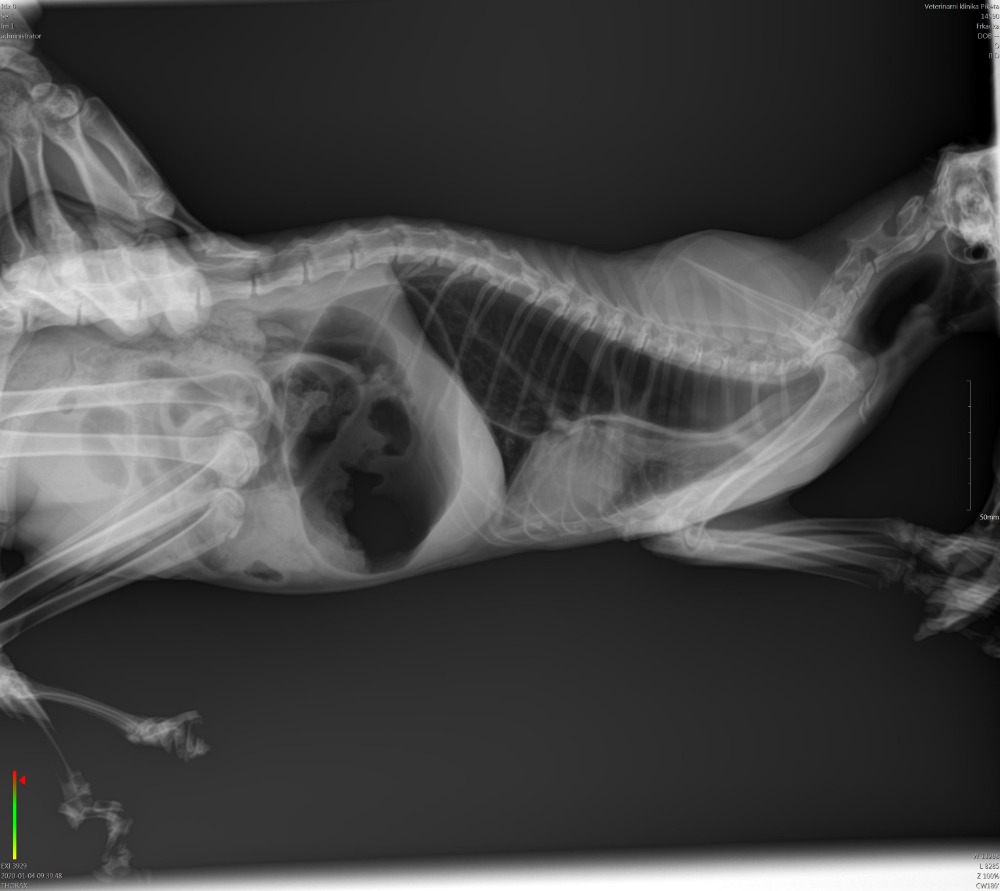

Dobrý den,našla jsem kočku ca 1rok starou. Špatně dýchá,občas pokašlává a tak jako chroptí. Občas to vypadá, že si ublinkne, ale ještě nezvracela. Jinak normálně jí, teplotu nemá. Byli jsme na veterině. Na jedné řekli,že vlastně nevědí, čím by to mohlo být. Nejspíš poúrazový stav. Další mi řekl, že to je selhávání funkčností měkkých orgánů , že se tak narodila a že se s tím nedá nic dělat. Neporadili byste mi prosím, co si myslíte. RTG přikládám. Děkuji Šteflová

Dobrý den. Ani já vám neřeknu dle toho jednoho snímku co by to mohlo být.Spíše by to chtělo více snímků z různých poloh / dorzoventrální poloha/, nebo CT vyšetř./.,sonograf.vyšetř., S pozdravem MVDr Jančík.